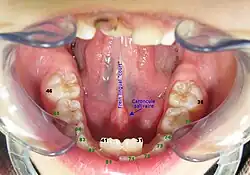

Chez l’homme, la caroncule lacrymale correspond à l’excroissance charnue située à l’angle interne de l’œil. Quant à la caroncule salivaire, elle se trouve au pied du frein lingual : elle supporte les orifices externes des glandes sublinguales et submandibulaires.